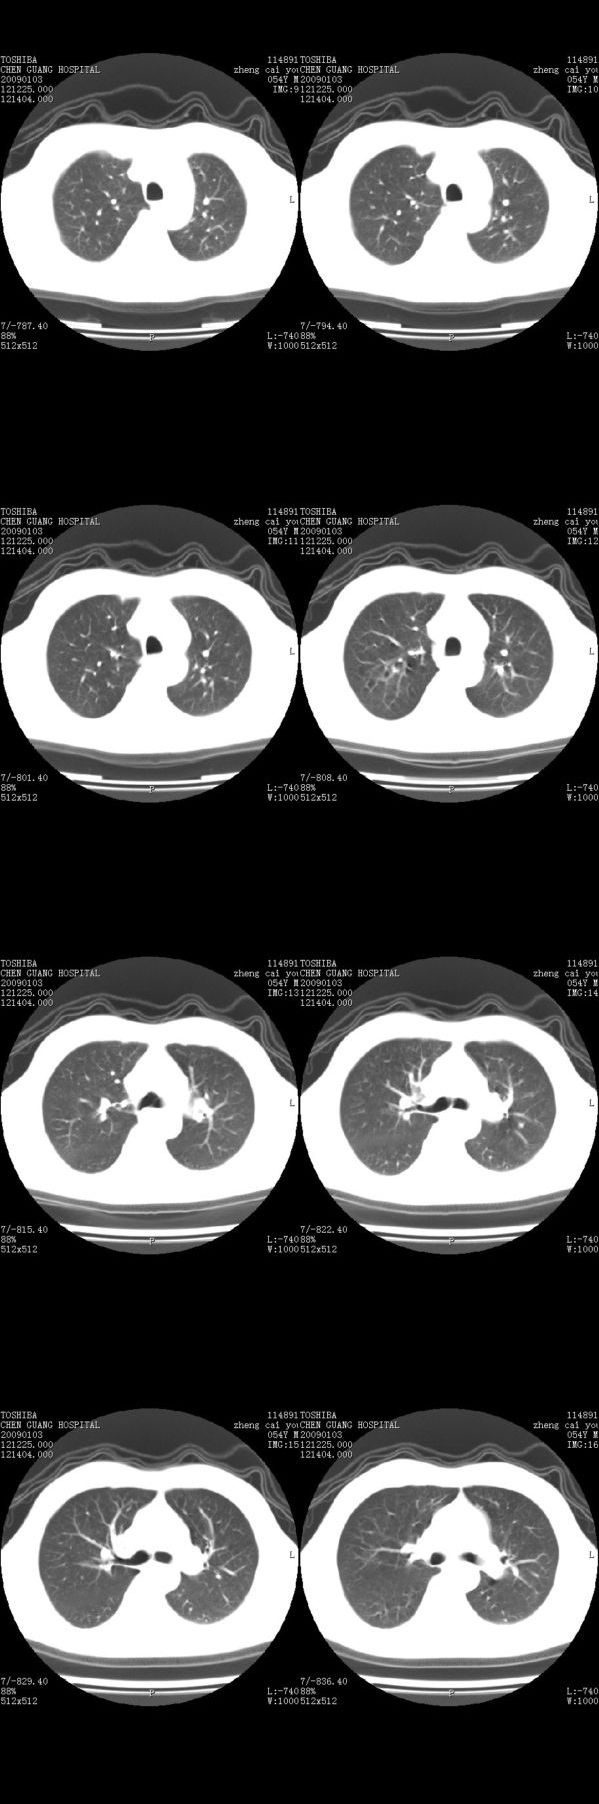

男,54岁,平时有吸烟后咳嗽、咯痰史,因右侧胸部(腋窝下)疼痛来检查平片,见右下肺动脉干起始处处结节,后到同学处做了平扫及增强。请各位老师帮忙看一下,不甚感谢!!!!!

支气管壁增厚

右肺下叶支气管扩张。

考虑------支气管壁增厚---局限性气肿---建议----气管镜进一步检查

增强了 但纵隔窗调的看不清  右上叶支气管壁似有增厚 警惕

肺窗薄扫、常规扫描均未见明确病变;右下肺门圆形与肺血管等密度影,考虑为血管变异;应该要纵隔窗才能进一步明辨。